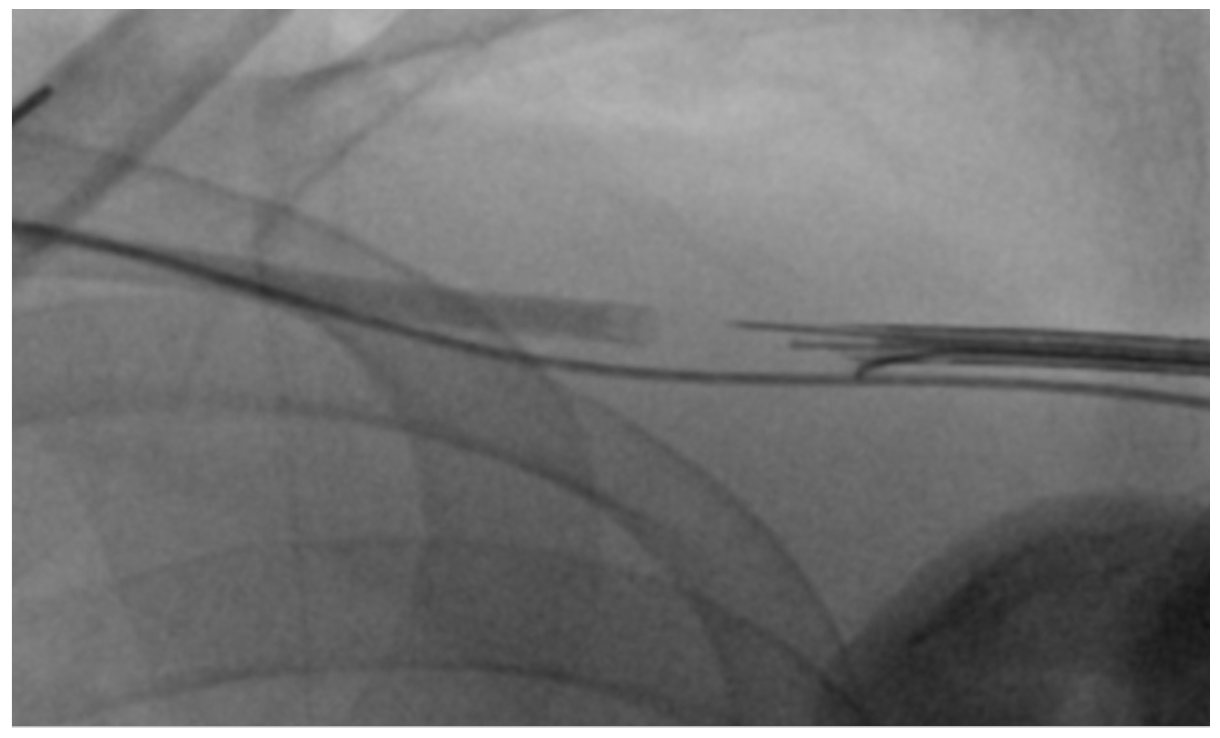

A 64-year-old female presented for closure of her left axillary access for intra-aortic balloon pump (IABP). We intended to close the access with standard balloon-assisted dry closure. A 7-Fr slender radial sheath was placed via left radial artery with a 7-mm peripheral balloon (Admiral; Medtronic) advanced to the subclavian artery. The IABP was removed over an 0.025-inch J-wire. There was already kinking noted at the entry site as indicated (Figure 1) due to adverse angulation. We failed to advance a Proglide device (Abbott) over an 0.035-inch wire due to kinking at transition zone of soft and hard part of the Proglide device (Figure 2).